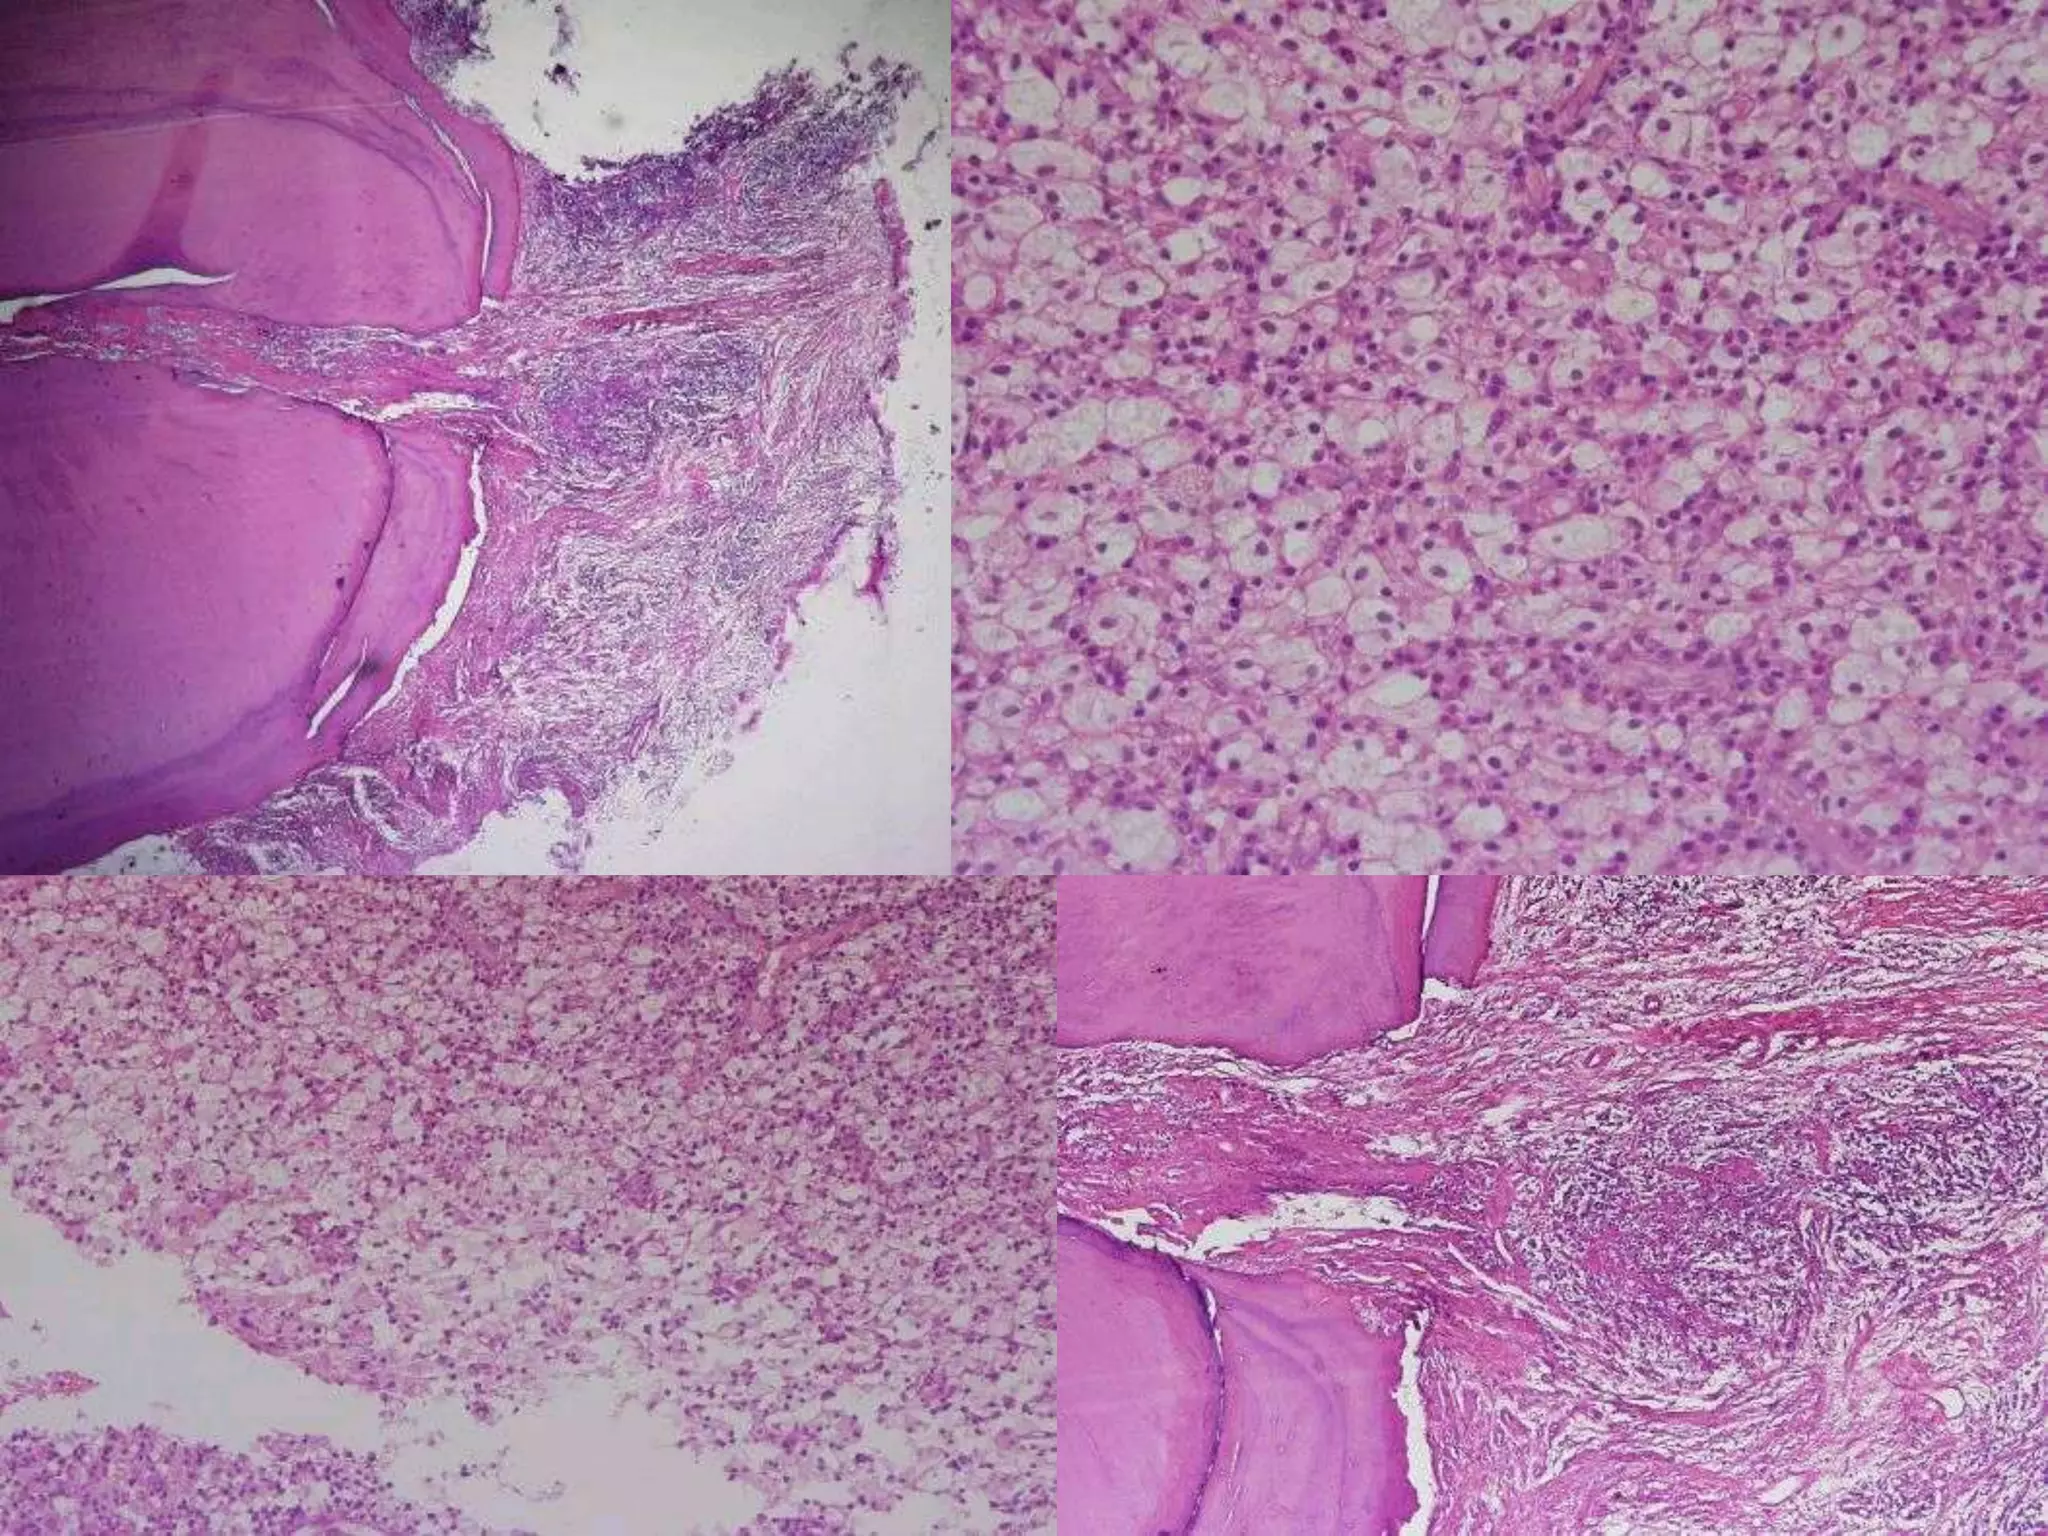

Periapical inflammation

Periapical

Granuloma

abscess

Chronic abscess or

osteomyelitis

Cellulitis

Skin or mucosal sinus

Bacteremia

Cyst

Acute Abscess

Etiology:

• Acute pulpitis. Chronic periapical lesions.

Clinical Features:

• Pain: sever and increases with percussion.

• Non-vital tooth.

• The tooth is slightly extruded in its socket.

• Fever, malaise & regional lymphadenitis.

• Osteomyelitis and swollen adjacent area.

Histopathological Features:

• Zone of liquefaction composed of:

▫ Exudates.

▫ Necrotic tissue.

▫ Dead neutrophils.

• Dilated blood vessels.

• Inflammatory [granular cell] infiltration.

Treatment:

• Drainage. Antibiotics. Supportive Tx.

Periapical inflammation Periapical Granuloma Periapical abscess Chronic abscessor osteomyelitis Cellulitis Skin or mucosal sinus Bacteremia Periapical Cyst

Acute Abscess Etiology: • Acutepulpitis. Chronic periapical lesions. Clinical Features: • Pain: sever and increases with percussion. • Non-vital tooth. • The tooth is slightly extruded in its socket. • Fever, malaise & regional lymphadenitis. • Osteomyelitis and swollen adjacent area. Histopathological Features: • Zone of liquefaction composed of: ▫ Exudates. ▫ Necrotic tissue. ▫ Dead neutrophils. • Dilated blood vessels. • Inflammatory [granular cell] infiltration. Treatment: • Drainage. Antibiotics. Supportive Tx.